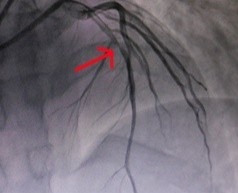

Hình ảnh chụp mạch của bệnh nhân trước khi được đặt stent mạch vành. Ảnh: BVCC.

Sau khi chụp mạch, bác sĩ phát hiện bệnh nhân bị hẹp 80% động mạch liên thất trước và có huyết khối trong lòng mạch. Các bác sĩ đã đặt stent mạch vành cho người bệnh. Sau can thiệp, hiện sức khỏe của anh V. ổn định, không còn tình trạng đau tức ngực.